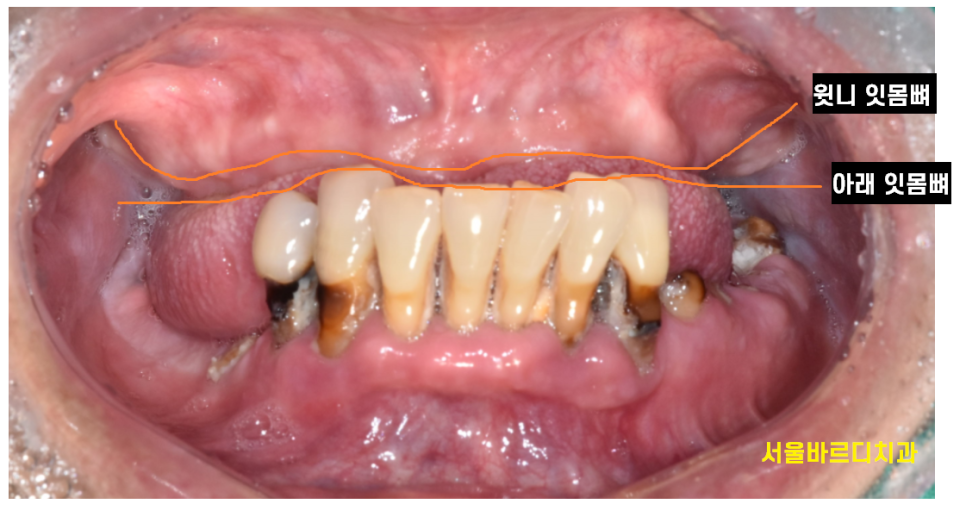

교합고경이 뭔지 사진 한장으로 설명드릴께요~

교합 = 앙 다물었을 때 상태

고경 = 수직 높이

위아래 치아를 물었을 때 위턱과 아래턱 사이의 거리를 뜻합니다.

교합고경이 무너진다는 것은

높이가 안나온다는것인데요.

오늘 환자분도 위아래 높이가 거의 차이가 없었습니다.